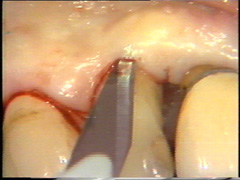

La incisión es entonces continuada en  bucal siguiendo la línea del margen gingival pero ubicando el corte en 1 a 1,5 mm hacia apical. La incisión debe partir de coronal del hueso alveolar en la  proximidad del diente. En el segundo premolar el bolsillo está muy profundo y aquí la incisión se ensancha para generar reducción de la bolsa  que luego es reemplazado por el colgajo.

La profundidad al sondaje en  los primeros premolares en bucal es poco profunda y aquí la incisión se ubica en el surco ginginval propiamente dicho. El escalpelo se mueve a través del tejido con un serrar suave y con pulso firme.